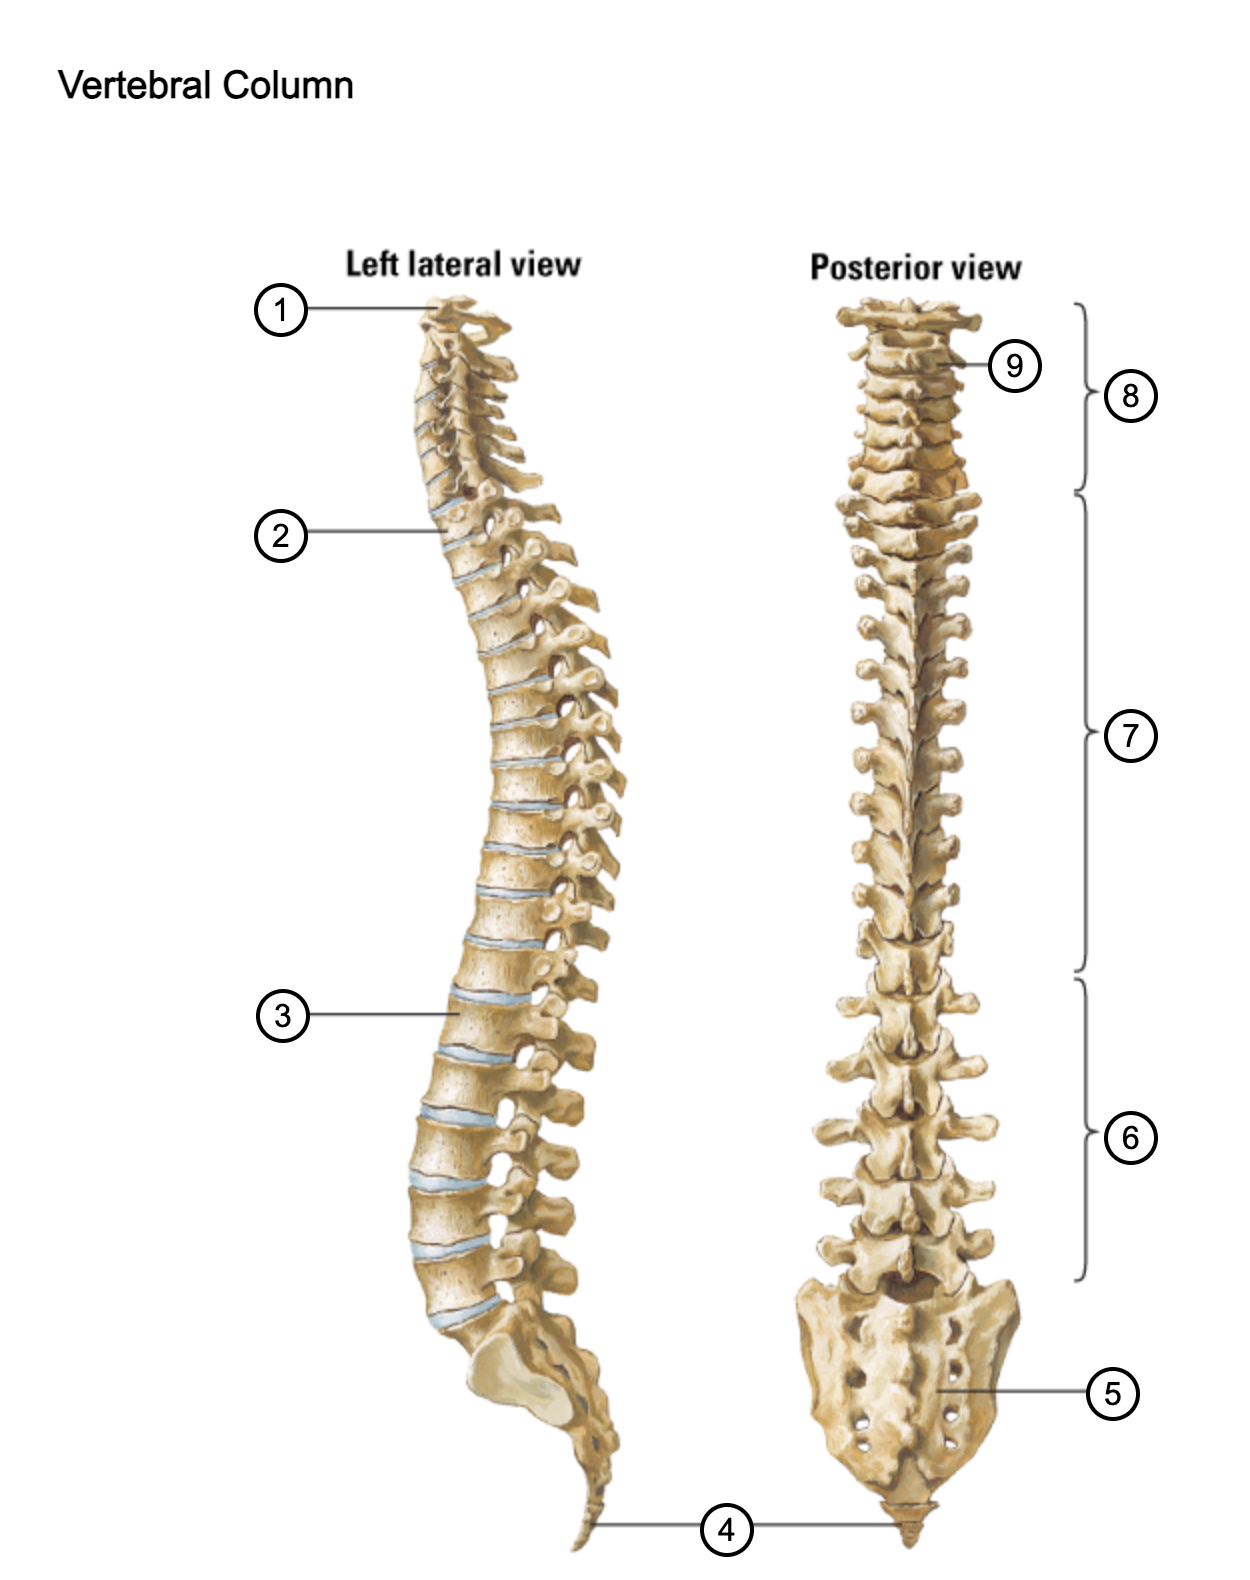

1

atlas (C1)

2

T1

3

L1

4

coccyx

5

sacrum (S1-5)

6

lumbar vertebrae

7

thoracic vertebrae

8

cervical vertebrae

9

axis (C2)